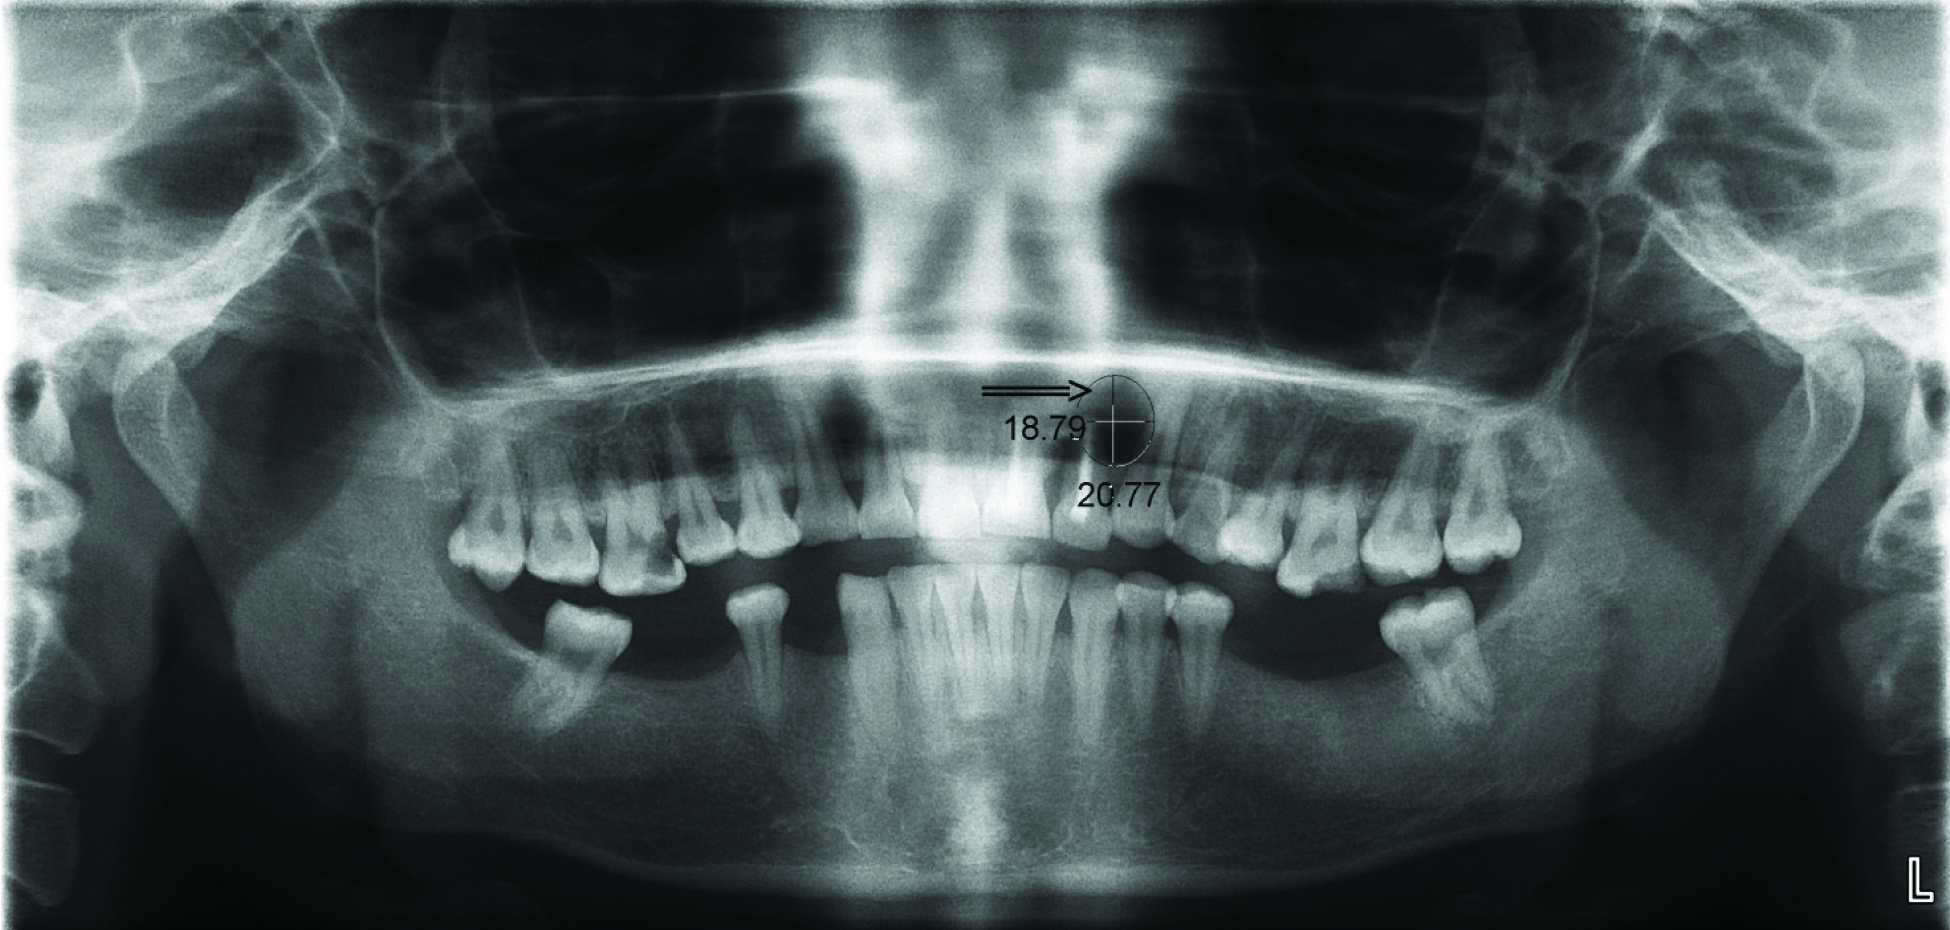

Preoperative and postoperative measurement of radiolucency of the periapical lesion was done at 0 and 3 months with digital orthopantomogram [Table/Fig-3,4]. PLANMECA- DIMAXIS SOFTWARE with version Pro 4.16 (2006) was used for this purpose for assessing periapical lesion on the basis of morphometric analysis for measuring height and width of radiolucency to resolution level up to 0.00mm. The distance from the crest of the bone, corresponding the apical 3rd of resected root to the basal bone, corresponding palatal aspect in digital orthopantomogram was measured as the length of radiolucency in the cyst. The maximum mesio-distal distance of radiolucency was measured as the width of radiolucency in the cyst. Magnification factor was calculated using the standard formula.

Pre operative orthopantomogram with yellow arrow shows large radiolucent lesion along left upper anterior teeth region.

Third month postoperative orthopantomogram with black arrow shows reduction in radiolucency with mixed radiopacity suggestive of bone formation at surgical defect.

| 1 | Length-28.75Width-31.22 | Length-20.77Width-18.79 |